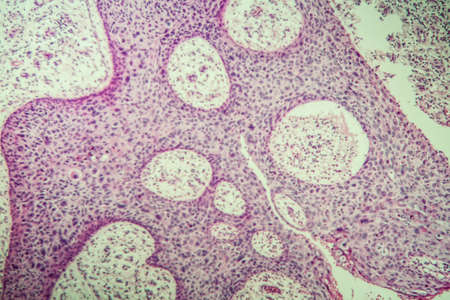

Bowen's Disease Tumor under the microscope 100x

Bowen's Disease Tumor under the microscope 100x